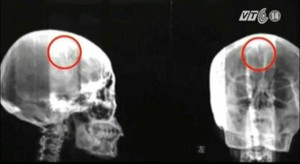

Một bệnh nhân người Trung Quốc sau một thời gian bị đau đầu dữ dội đã đi khám bác sĩ và phát hiện ra 1 chiếc kim dài 5cm nằm trong não.